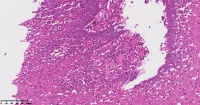

一般病史食道溃疡性质待查

标本名称食道溃疡性质待查

考虑炎性病变,高倍镜下找找看有没有念珠菌。

溃疡伴局部上皮低级别。

应该是炎症

大量嗜酸性粒细胞浸润,查找原因

食管溃疡,嗜酸细胞性食管炎,总体感觉还是炎症引起的不典型